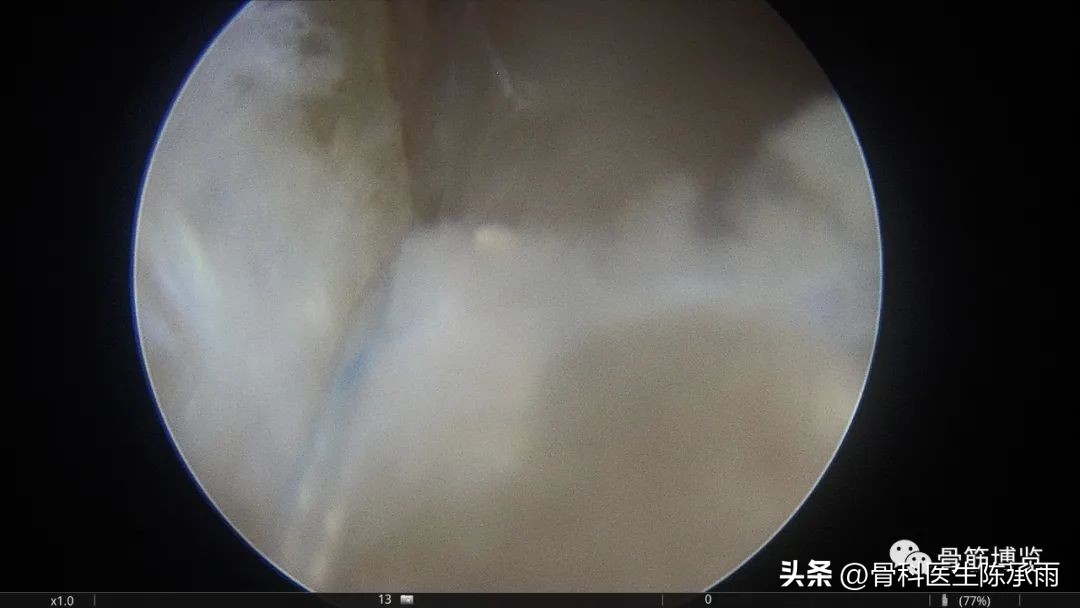

术中情况

取出游离关节面,为股骨外侧髁非负重区脱落的关节面

术中C臂定位

髌骨内侧支持带重建前的髌骨脱位情况

髌骨内侧支持带重建后的情况